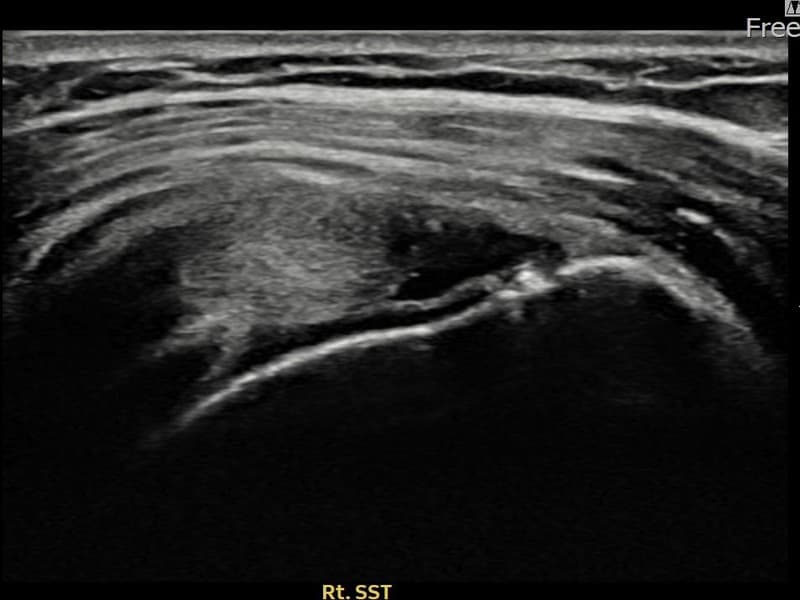

施術前

術前超音波にて右 棘上筋腱 関節面側部分断裂・右肩棘上筋腱のエコー不連続と腱欠損(12mm × 4mm (腱厚の約48%欠損))を確認。術後超音波では断裂部位が再生組織で充填され、腱の連続性回復とエコーパターンの正常化が確認されました。